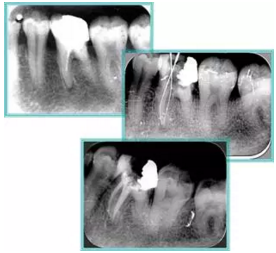

6. 鈣化

常見有修復(fù)性鈣化和增齡性鈣化。下面為根管鈣化 X 線片。

7. 器械折斷

右圖及下圖為器械折斷的 X 線片。箭頭處示折斷器械。